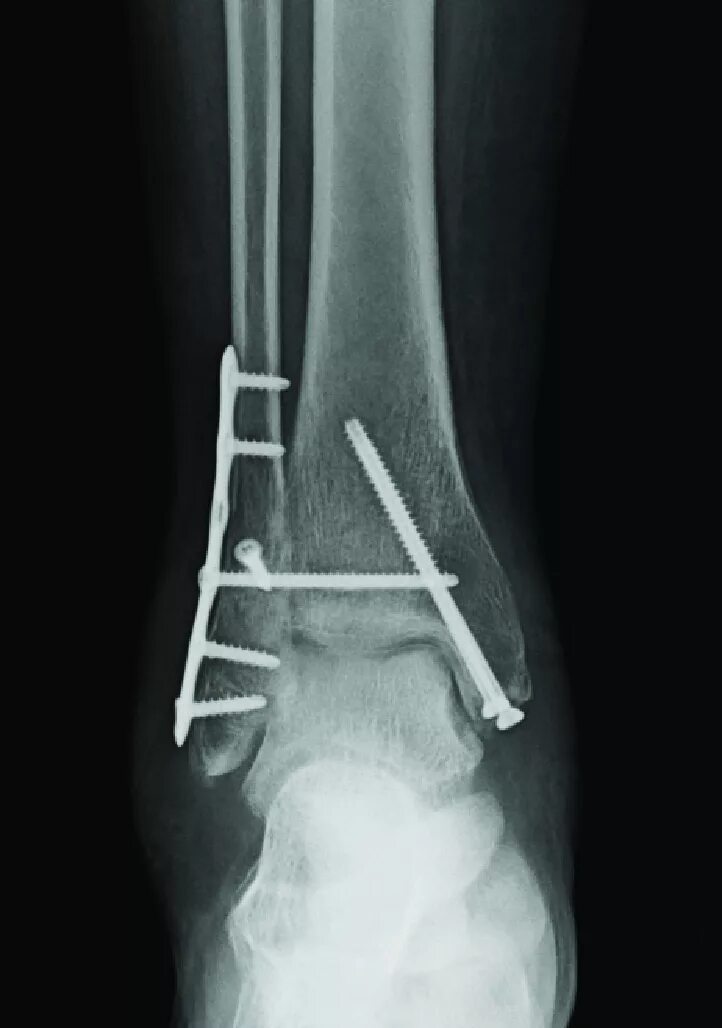

После остеосинтеза лодыжек